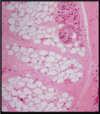

Explain this image

At the upper left corner is a low magnification of a cross section of the umbilical cord in which major blood vessels are visible. The mucoid tissue consists of fibroblasts and mesenchyme cells embedded within a gelatin-like extracellular matrix rich in collagen fibers. Note the simple cuboidal layer of the amniotic cells that cover the umbilical cord.

Explain this image

Mucoid connective tissue. Collagen fibers, appeared light blue, are visible among the fibroblasts. Simple cuboidal amniotic cells are visible at the upper left corner. Trichrome stain.

Explain this image

Mucous tissue. A section of an umbilical cord showing fibroblasts surrounded by a large amount of loose extracellular matrix composed of ground substance and collagen fibers. H&E stain.